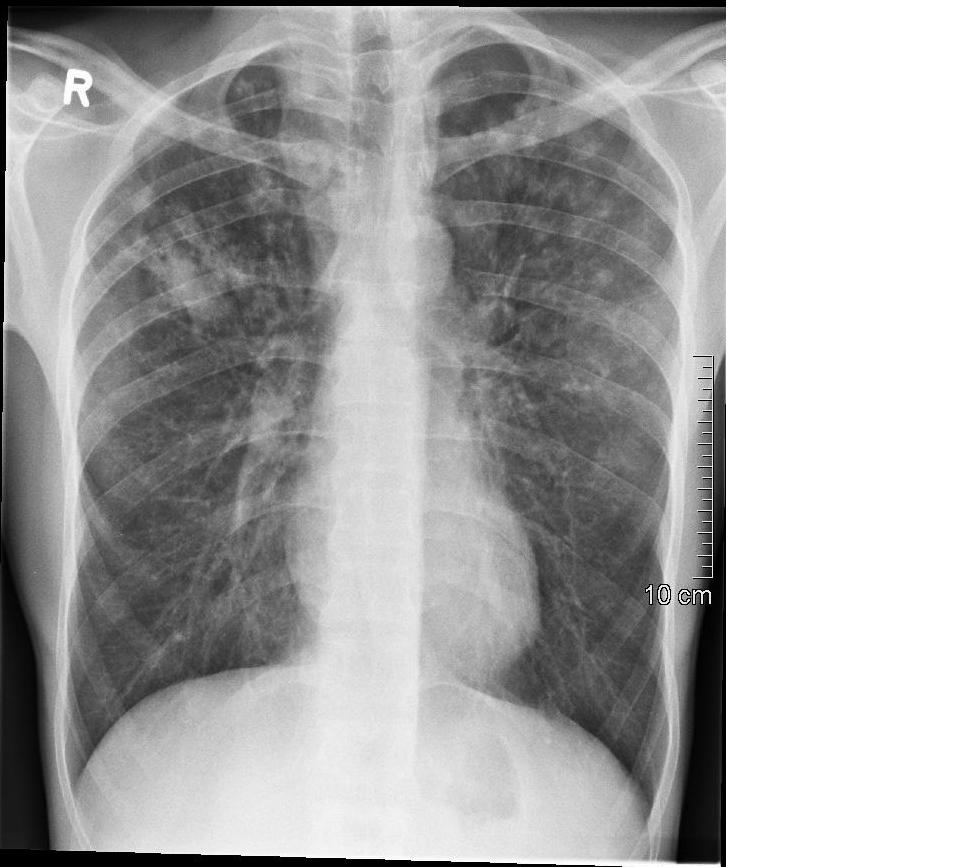

Chest X Ray Before And After Tb Treatment . Find out the effectiveness, procedure, and. However, the radiographs may be normal or show only mild or nonspecific. (a) ap chest radiograph of a child at presentation,. Right paratracheal and hilar lymphadenopathy before and after treatment. Chest radiographs play a major role in the screening, diagnosis, and response to treatment of patients with tb.

However, the radiographs may be normal or show only mild or nonspecific. Find out the effectiveness, procedure, and. (a) ap chest radiograph of a child at presentation,. Chest radiographs play a major role in the screening, diagnosis, and response to treatment of patients with tb. Right paratracheal and hilar lymphadenopathy before and after treatment.

Chest X Ray Before And After Tb Treatment Chest radiographs play a major role in the screening, diagnosis, and response to treatment of patients with tb. Chest radiographs play a major role in the screening, diagnosis, and response to treatment of patients with tb. (a) ap chest radiograph of a child at presentation,. Find out the effectiveness, procedure, and. However, the radiographs may be normal or show only mild or nonspecific. Right paratracheal and hilar lymphadenopathy before and after treatment.